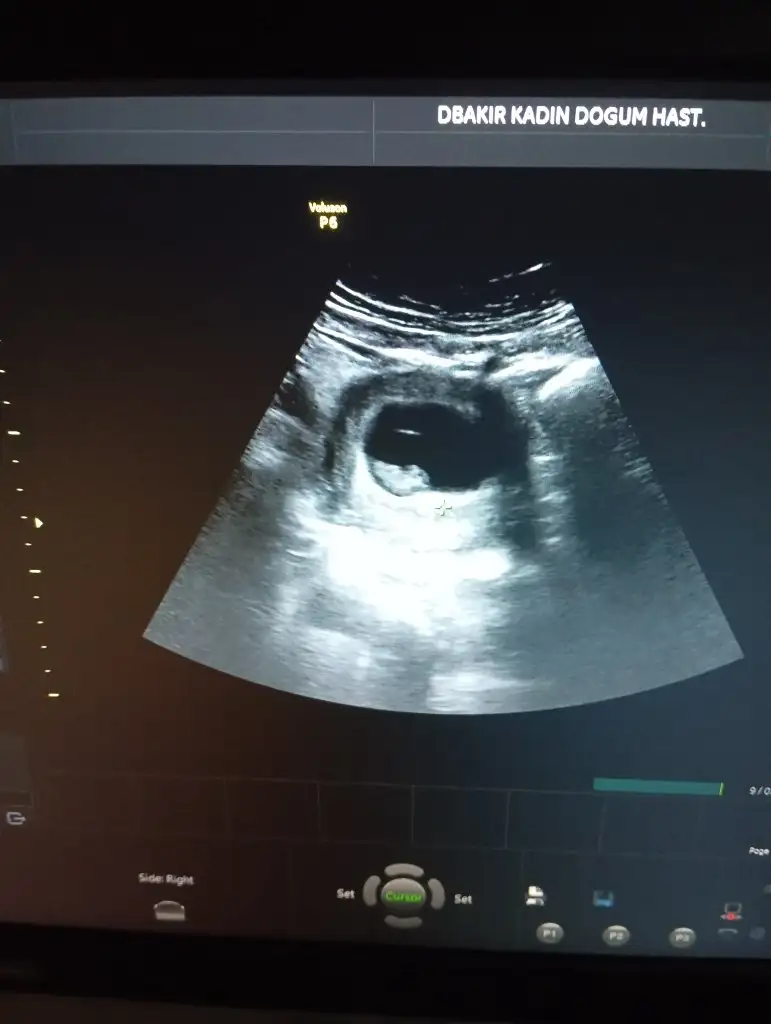

Kese uzunsa erkek yuvarlaksa kız mi ?

Kızlar bı arkadaş keseye göre tahmin yapıyor ve hep tutuyormuş iki oğlunu da bu şekilde cok yeniyken bile tahmin etmiş...ogullarinda kesesi hep uzunmuş muz gibi...yuvarlak ve yuvarlağa yakın olanlar hep kızdır diyor..ve bayağı emin konusuyor..benimki şişman bı fasulye gibi oo kesin kız görürsün dedi...sizlerin keselerinin şekli nasıldı ve cinsiyet neydi konusalimmi 😊